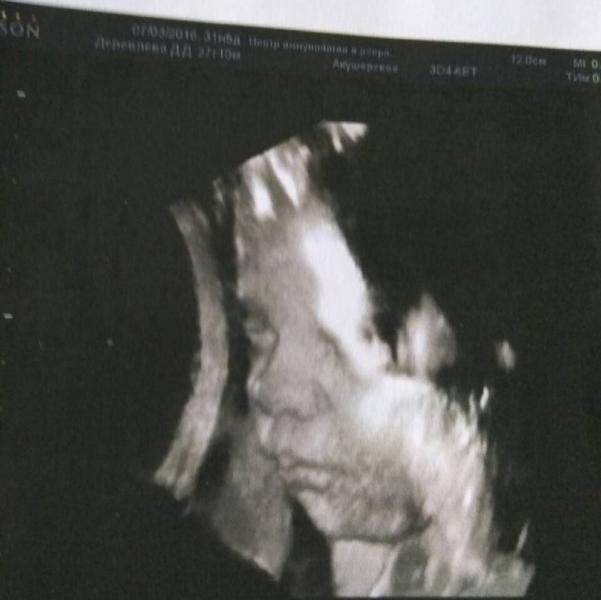

ура,сходили на 3 узи)))все у нас хорошо...лежим головой вниз,без обвитий и т.д. короче,ВСЕ ХОРОШО...весим 2010,сказали не перекормить ,а иначе не смогу сама и светит кс...блин,так я за 1,5 недели наоборот даже похудела на 1700...может это витамины?...